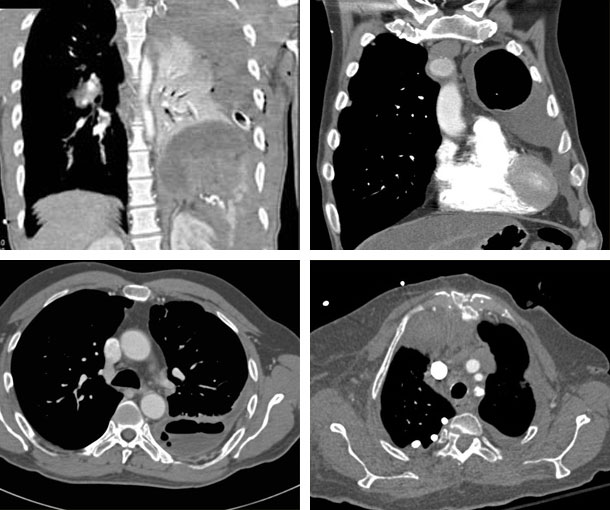

Chest CT Appearances

Pleural Empyema CT Findings

- Atypical pleural effusions along the mediastinum

- Pleural enhancement

- Pleural thickening > 4mm

- Fissure loculations

- Fat stranding

- Gas bubbles or microbubbles in the pleural space

- Layers of the pleura split around a collection of fluid (“split pleura” sign)